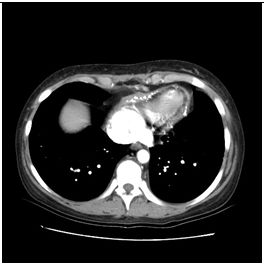

1. 病人62歲,男性,在6月8日清晨6時突然有嚴厲胸疼發生,以致醒來起床,隨即發生冒汗、噁 心、嘔吐及腹痛,乃急往醫院求治。病人有高血壓及貧血病史。理學檢查顯示急病面容,血壓250/100 mmHg,心跳67/min,心肺並無任何異常,但腹部腸蠕動聲減少,而且有腹肌難碰之狀,右腳踝dorsalis pedis脈動消失。胸部X光及心電圖如示。其他影像如圖 。血液檢查,AST 29 U/L;CK 102.0 U/L;CK-MB 22.4 U/L;Troponin I <0.04 μg/L;Amylase 80 U/L;Lipase 32 U/L;Na 3.3 mEq/L;K 3.3 mEq/L;D-dimer 12-24 μg/ml ;BUN 53.6 mg/dl;Creatinine 2.6mg/dl。病人服用Clondine (0.075 mg) 6#bid; Doxazosin (1 mg) 2#hs;Amlodipine (5 mg) 1#bid;Trichlorthiazide (2 mg) 1#qd;Minoxidil (10 mg)2#bid;Valsartan 1#qd; Metoprolol (100 mg) 1/2#qd。請問本病人最可能的診斷是: (A) 急性心肌梗塞 (B) 肺動脈栓塞合併肺動脈高血壓 (C) 急性心衰竭症 (D) 主動脈剝離 (E) 惡性高血壓